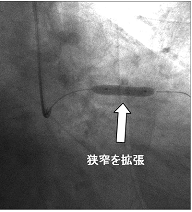

冠動脈造影検査を施行したところ、下図のように冠動脈に狭窄が見つかりました。

内服薬では、症状が改善しないためカテーテル治療を行うこととしました。

ガイドワイヤー(先端がやわらかくなった針金)を冠動脈に挿入します。針金といっても血管を傷つけないように先端は髪の毛のような柔らかさです。

狭くなった部分を風船で拡張した後に、ステントと呼ばれる金網の筒を留置しました。